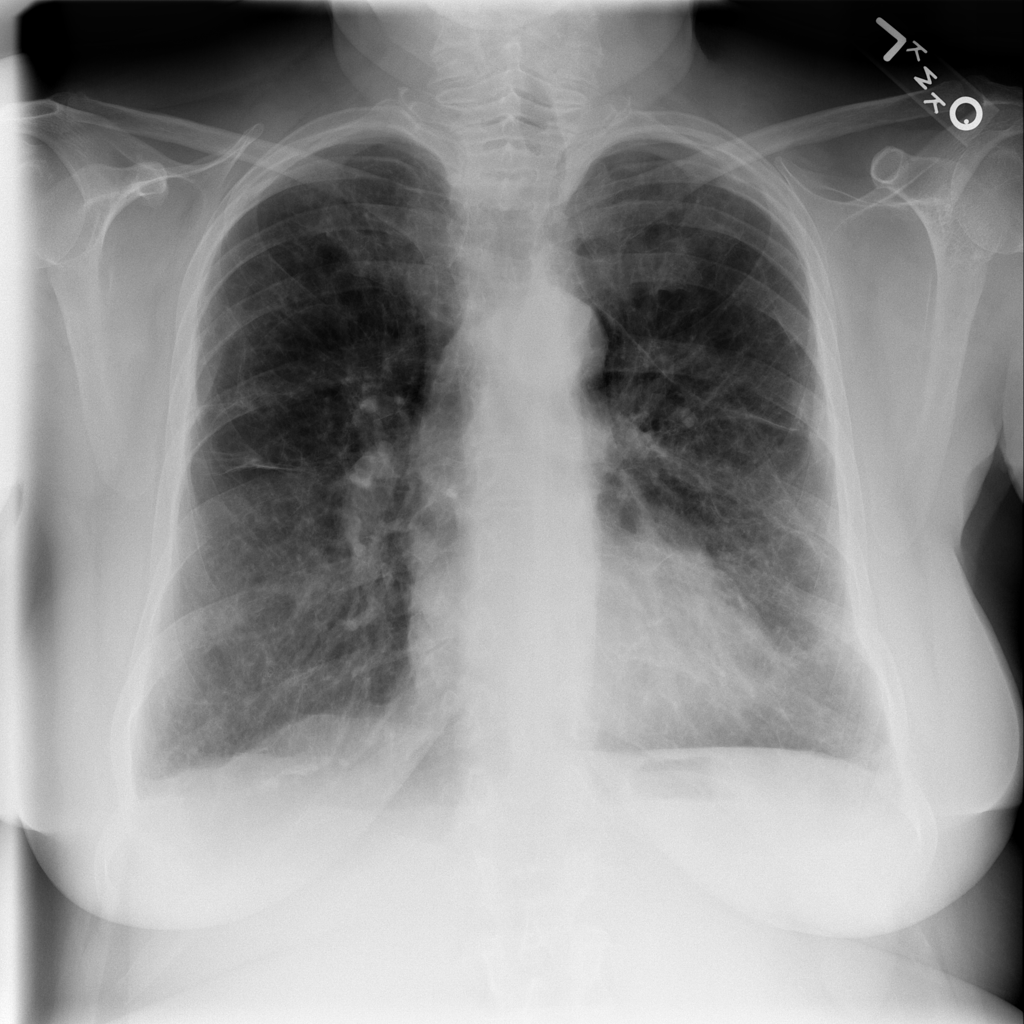

PAT-84DB · IMG-003Pneumonia

PAT-84DB · IMG-003

PA